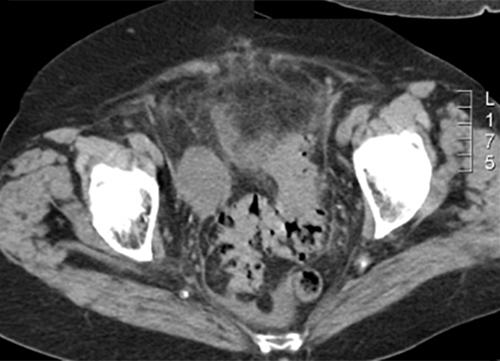

Monsieur A., 53 ans, est adressé aux urgences par son médecin traitant pour des douleurs abdominales fébriles. Celles-ci sont localisées en fosse iliaque gauche et hypogastre. Elles évoluent depuis quelques jours mais sont devenues plus intenses depuis vingt-quatre heures.

Cliniquement, il a une température à 38,2 °C, l’abdomen n’est pas distendu mais la palpation retrouve une franche douleur en fosse iliaque gauche et en hypogastre sans défense. Il n’y a pas de signe fonctionnel urinaire.

Le diagnostic est tout à fait possible, à évoquer ici en première intention devant l’âge (> 40 ans) et la symptomatologie (douleurs fébriles en fosse iliaque gauche et hypogastre).

– de la localisation de la douleur en fosse iliaque gauche ;

– du syndrome inflammatoire : fièvre à 38,5 °C avec hyperleucocytose à la biologie ;

– de l’argument de fréquence de cette pathologie à cet âge (la prévalence des diverticules sigmoïdiens est de plus en plus importante avec l’âge, après 40 ans).